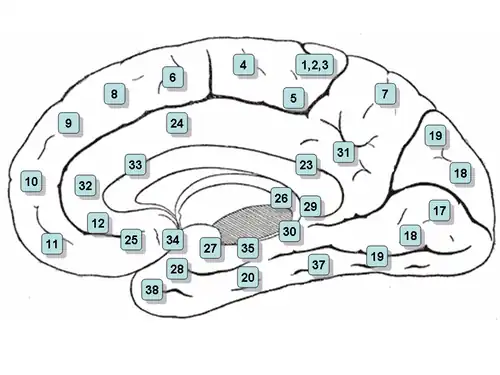

Medial surface of the brain with Brodmann's areas numbered. | |

It is the 25th "Brodmann area" defined by Korbinian Brodmann. BA25 is located in the cingulate region as a narrow band in the caudal portion of the subcallosal area adjacent to the paraterminal gyrus. The posterior parolfactory sulcus separates the paraterminal gyrus from BA25. Rostrally it is bound by the prefrontal area 11 of Brodmann.[1]